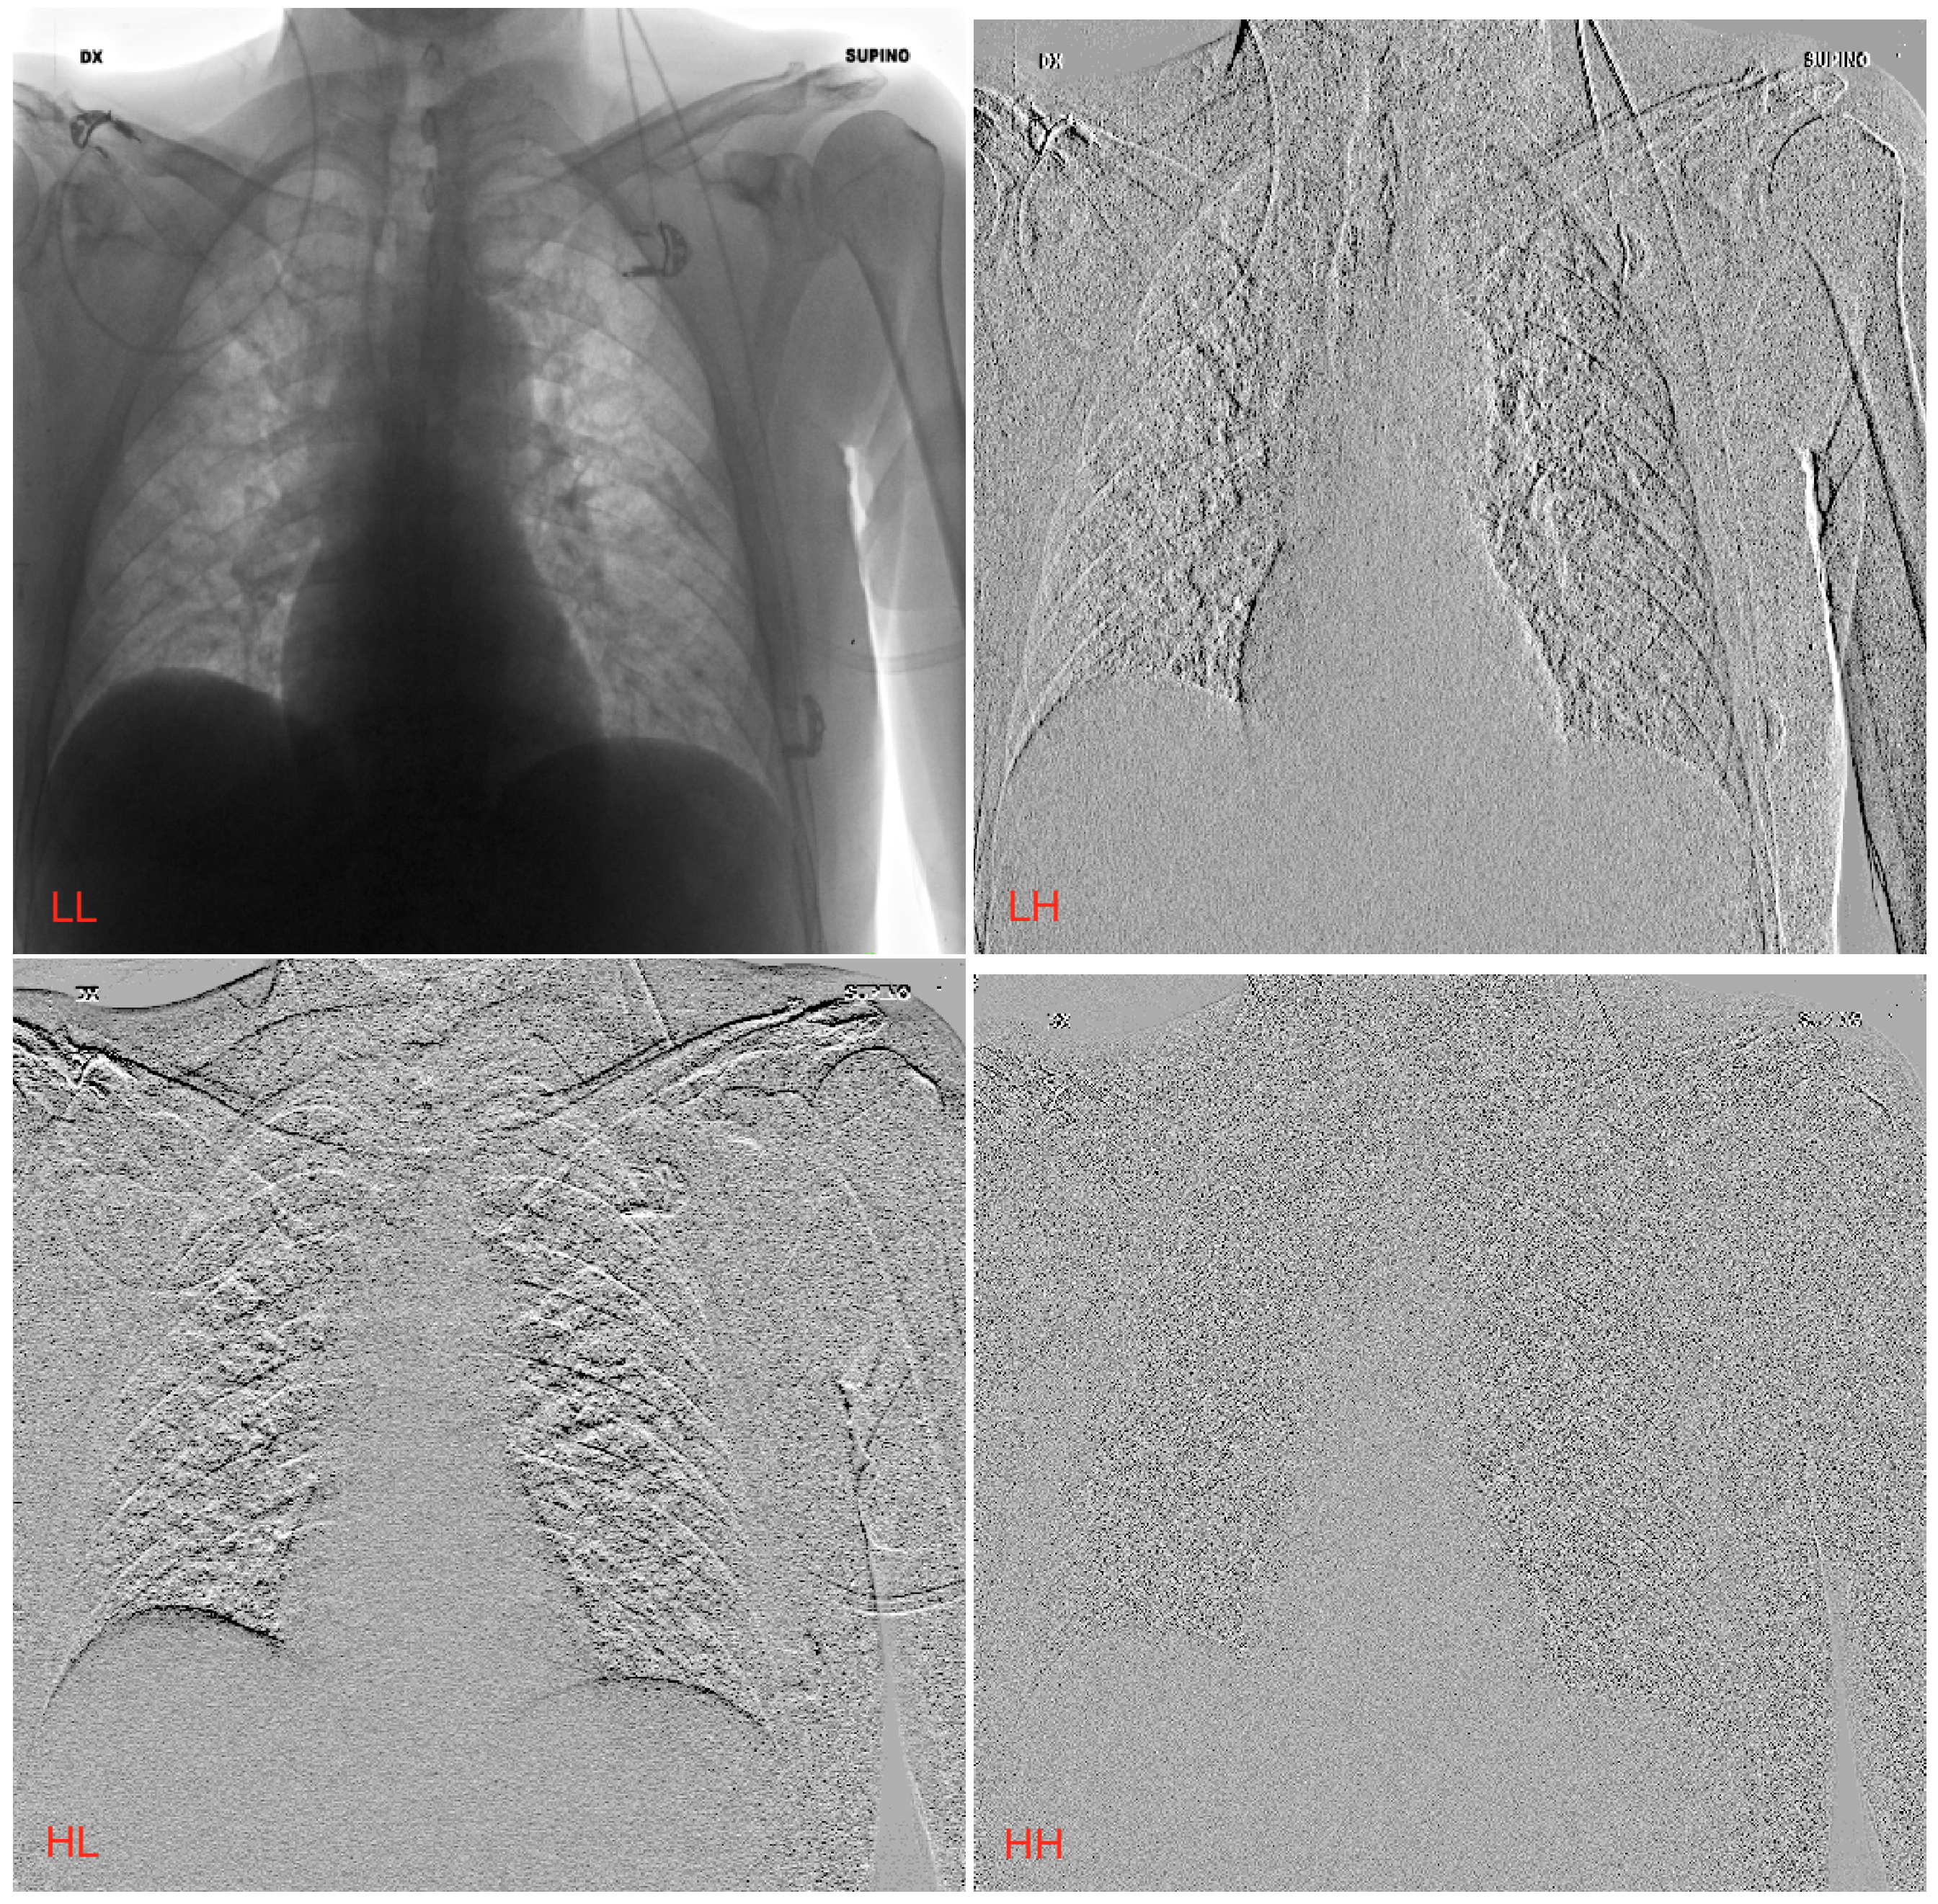

2.2. Wavelet Transform